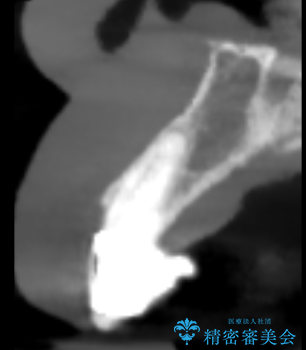

- 歯茎の大きな腫れを主訴に来院された患者様です。前歯5本にはブリッジが装着されていました。レントゲン検査より、右上3番に大きな根尖病巣が認められ、さらに左上1、2番の支台歯にも破折があったため、抜歯を行いました。その後、インプラントを3本埋入し、オールセラミッククラウンのブリッジで補綴しました。

術前のCT画像より、抜歯即時インプラントが可能と判断したため、抜歯と同時にインプラント埋入を行いました。術式にはセミルーナーフラップを用い、唇側の骨吸収を抑える目的でルートメンブレンテクニックを併用しました。